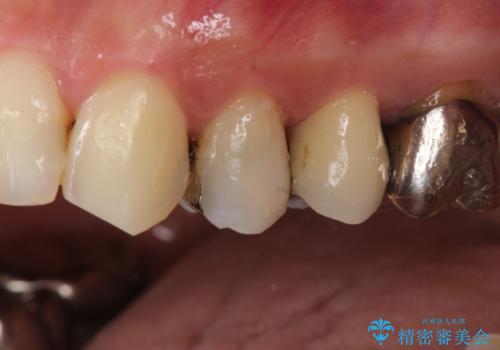

大きい虫歯 根管治療〜オールセラミッククラウン

- 大きな虫歯を認めた患者様です。

自発痛を認めたことから、不可逆性歯髄炎の診断を行い治療を介入しております。

根管治療した場合は速やかに被せ物による修復が必要です。